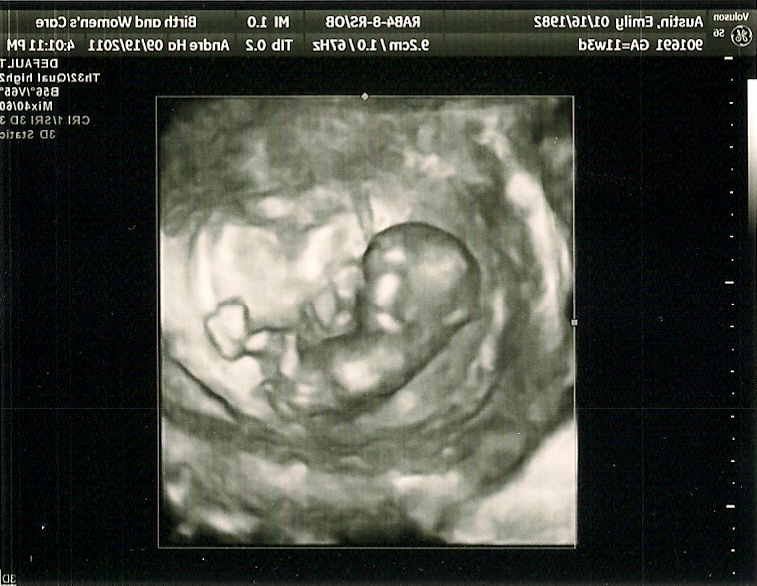

- Later in July: BEBE!!!!!!!! After making an active effort at making a baby for only over two months, we learned of the existence of our little angel. We had probably only unpacked the last box from moving a couple of days before. The fun never ends! This ultrasound is of Beebs when she was only about ten weeks old.